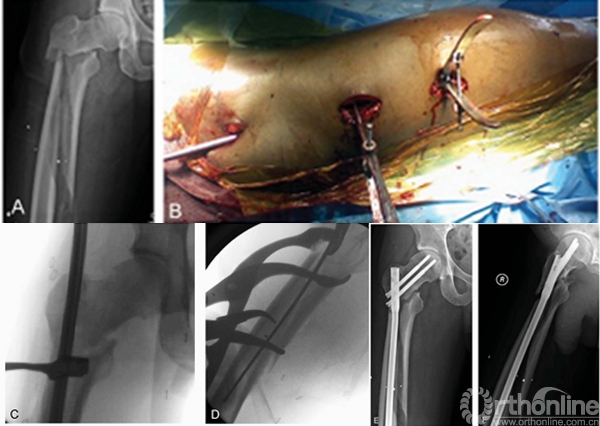

肖XX,男,35岁

术后

术后1年

生物力学研究表明:髓内钉+适当的环扎带能够降低复位后的骨折再次移位、骨不连和内固定失败的几率。

2.辅助捆绑带或阻挡钉能增加骨折稳定性促进愈合;